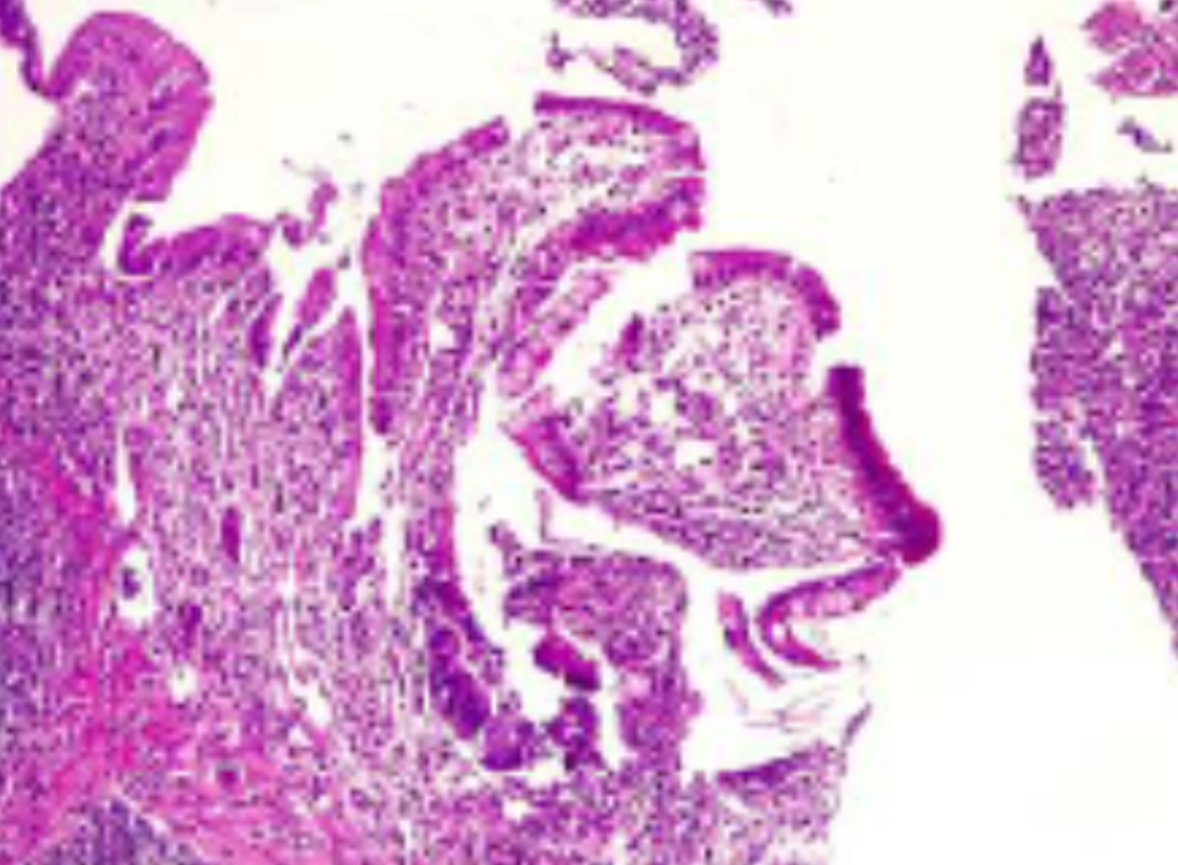

Method: We present a 62-years old male patient with hepatitis C-virus (HCV) cirrhosis and successfully downstaged to Milan criteria HCC. Orthotopic liver transplantation was performed after 6 months of surveillance and discharged uneventfully after 7 days. One month later patient developed abdominal cramps, diarrhea and cutaneous erythema. Mild leukopenia with normal liver and renal function, blood and stool samples were negative, clostridium and other pathogens were also ruled out. Abdominal CT-scan showed moderate distal ileum and colon wall edema. At colonoscopy stellate ulcers was found, biopsy was taken as well to skin lesions. Colon biopsy showed acute inflammation with severe mucosal damage and apoptosis. Skin biopsy showed interphase vacuolar dermatitis. GVHD was suspected and donor lymphocyte chimerism was positive with 5%.